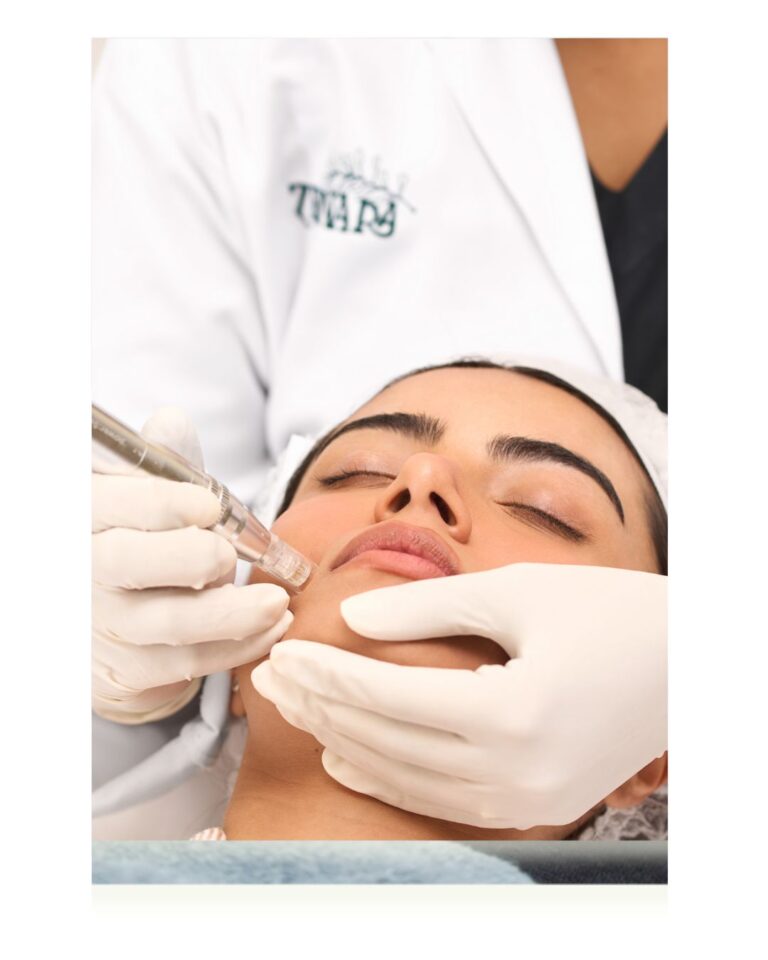

Achieve even, radiant skin tone with advanced pigmentation treatments. Remove dark spots, melasma, and sun damage for a luminous complexion.

Pigmentation treatment is a specialized medical approach to reducing unwanted dark spots, uneven skin tone, and hyperpigmentation. Using advanced technologies like laser therapy, chemical peels, topical treatments, and medical-grade skincare, our dermatologists target excess melanin production to reveal brighter, more even-toned skin.

Pigmentation Treatment at Zennara is a comprehensive solution for achieving clear, even-toned, radiant skin. Our medical-grade treatments deliver visible, lasting results by targeting pigmentation at its source.

Experience transformative skin brightening with proven medical benefits